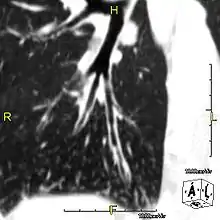

Sagittal CT image showing "tree in bud" appearance of mucous impaction in distal small airways related to primary ciliary dyskinesia

Around 80% of people with primary ciliary dyskinesia experience respiratory problems beginning within a day of birth. Many have a collapsed lobe of the lung and blood oxygen low enough to require treatment with supplemental oxygen.[1] Within the first few months of life, most develop a chronic mucus-producing cough and runny nose.[1] The main consequence of impaired ciliary function is reduced or absent mucus clearance from the lungs, and susceptibility to chronic recurrent respiratory infections, including sinusitis, bronchitis, pneumonia, and otitis media. Progressive damage to the respiratory system is common, including progressive bronchiectasis beginning in early childhood, and sinus disease (sometimes becoming severe in adults). However, diagnosis is often missed early in life despite the characteristic signs and symptoms.[2] In males, immotility of sperm can lead to infertility, although conception remains possible through the use of in vitro fertilization, there also are reported cases where sperm were able to move.[8] Trials have also shown that there is a marked reduction in fertility in females with Kartagener's syndrome due to dysfunction of the oviductal cilia.[9]